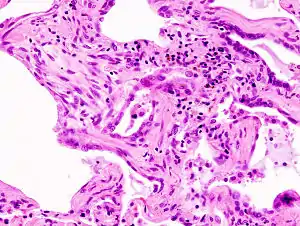

![]() | |

| End-stage pulmonary fibrosis of unknown origin, taken from an autopsy | |

Prolonged ILD may result in pulmonary fibrosis, but this is not always the case. Idiopathic pulmonary fibrosis is interstitial lung disease for which no obvious cause can be identified (idiopathic) and is associated with typical findings both radiographic (basal and pleural-based fibrosis with honeycombing) and pathologic (temporally and spatially heterogeneous fibrosis, histopathologic honeycombing, and fibroblastic foci).